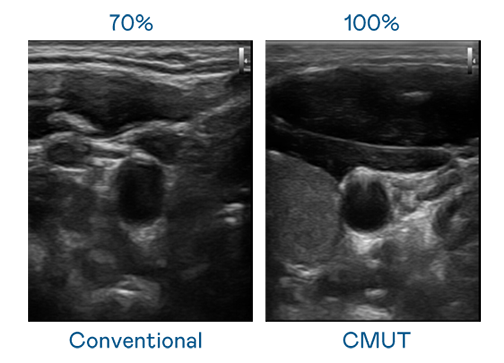

CMUT 技术是一种用电容式微机电元件来产生超音波讯号的技术。与传统 PZT 压电式技术相比,CMUT 频宽增加 30%,更宽频的超音波讯号让影像解析度大幅提升,是实现高影像品质医疗超音波扫描、促进精准医疗发展的关键技术。

超音波影像的解析度高低,首先取决于探头能发出的讯号频宽。304永利集团 CMUT 可提供高清晰的超音波讯号,提供高频宽、高灵敏度、影像纹理细节更高的超音波影像,协助医护人员缩短影像判读时间及利用精准的医疗影像进行诊断。